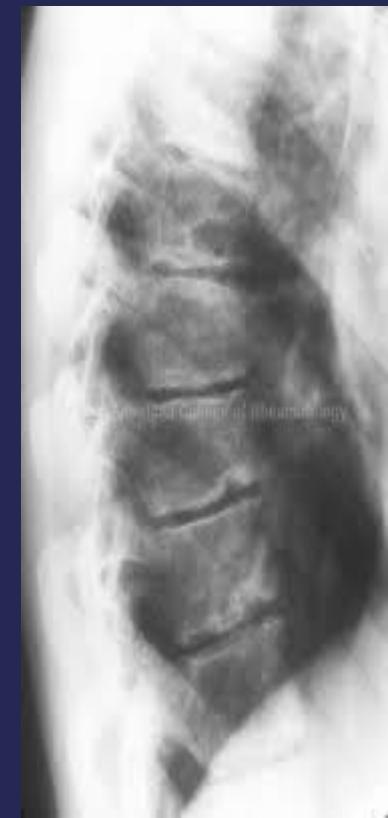

Scheuermann’s Disease

Pathology

- Irregular ossification of vertebral body epiphysis

- Central herniation of disc material into the body (Schmorl’s Node)

- Wedging of vertebrae

X-ray Findings

- Schmorl’s nodes (central disc herniation)

- Vertebral wedging